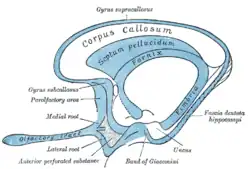

Scheme of rhinencephalon (anterior perforated substance labeled at bottom left) | |

The anterior perforated substance is a part of the brain. It is bilateral. It is irregular and quadrilateral. It lies in front of the optic tract and behind the olfactory trigone.

Structure

The anterior perforated substance is bilateral. It lies in front of the optic tract. It lies behind the olfactory trigone,[1] separated by the fissure prima. Medially and in front, it is continuous with the subcallosal gyrus.[2] Laterally, it is bounded by the lateral stria of the olfactory tract, and is continued into the uncus.[2]

Its gray substance is confluent above with that of the corpus striatum, and is perforated anteriorly by numerous small blood vessels that supply such areas as the internal capsule.